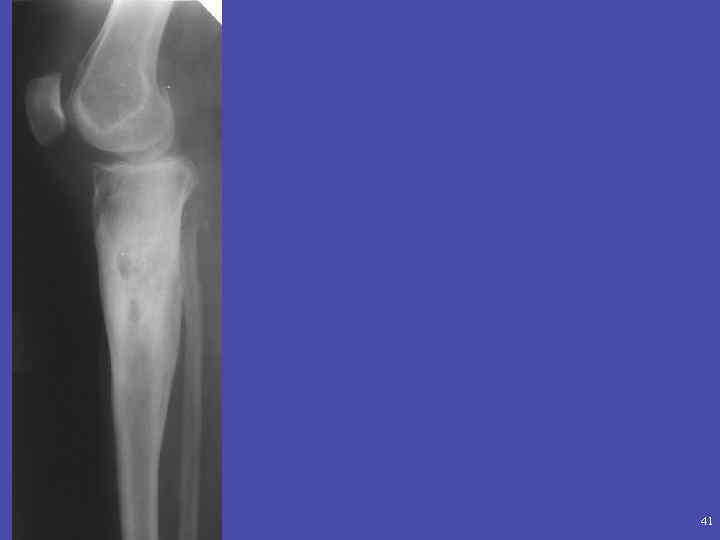

41

Абсцесс Броди. Локализованный тип подострого или хронического остеомиелита, как правило, вызываемый стафилококком. Рентгенологически: участок просветления чаще округлой формы, со склеротическим ободком, расположенный чаще в метафизе. Размеры: от 1 см до 4 см. Содержимое: серозное или серозно-гнойное, без секвестров. Выделяют 4 типа:

Дифференциальная диагностика: -эозинофильная гранулема – -остеоид-остеома-фиброзная дисплазия, не оссифицированная фиброма- хондробластома-ОБК-аневризматическая киста -саркома Юинга